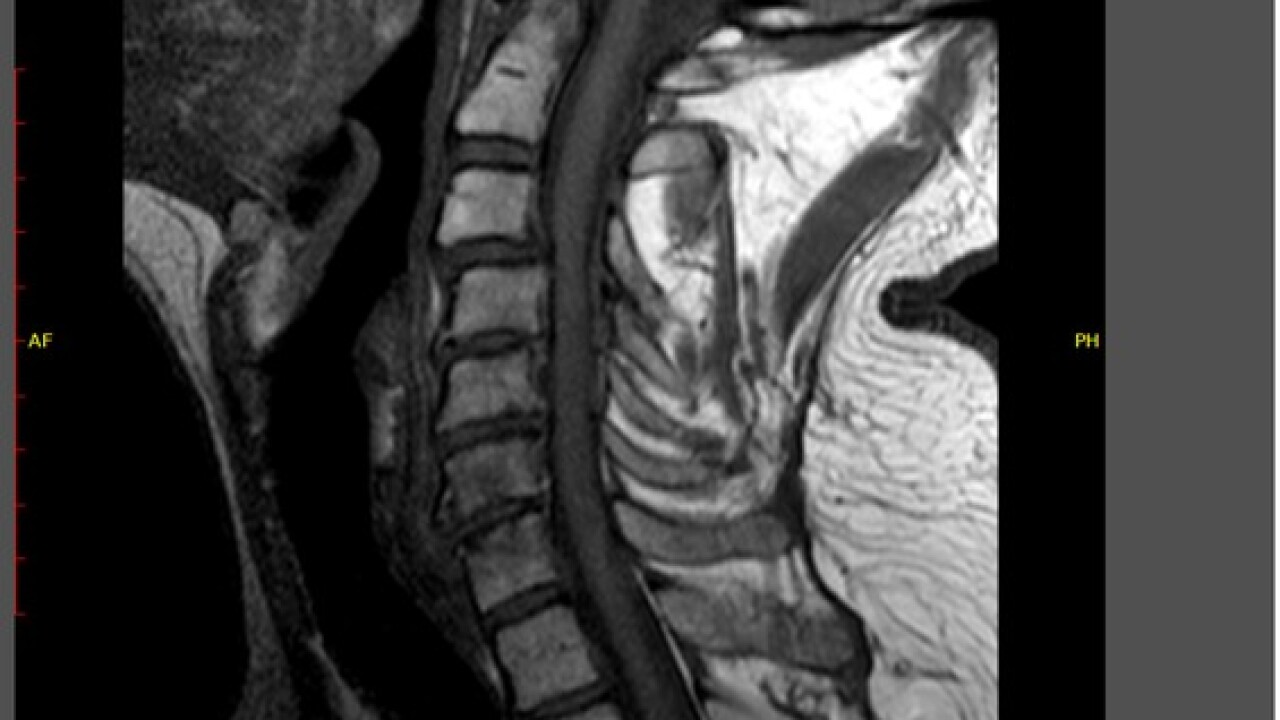

And sure if enough, when he finally got one it shows multiple discs in his neck damaged, at least two pinching his spinal cord.

A workers' comp doctor confirmed his "symptoms are a direct result of the incident he described as occurring" on the job. Even so, workers' comp did not approve the MRI until months later and surgery until 82 days after his injury.

"It created white matter damage," says Robert. "Doctors said that's going to be dead. I'm going to have nerve issues for the remainder of my life."